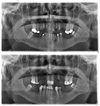

En comparant les 2 radiogrammes panoramiques, pris sur 6 mois d’écart, nous

avons pu constater une amélioration de l’état des condyles : densité osseuse, mobilité de la mandibule récupérée dans les 3 dimensions de l’espace. Ce qui était impossible avant.